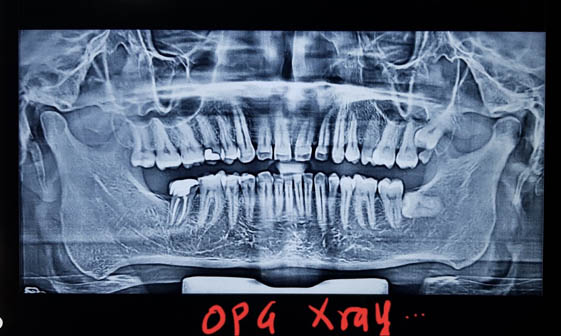

याशिवाय माणसाच्या उत्क्रांती मुळे कमी होणाऱ्या जबड्यांच्या आकारावर दातांची संख्या तेवढीच म्हणजे 32 राहिल्यामुळे सर्वात शेवटी उगवणाऱ्या अक्कलदाढा अडकल्यामुळे ,किंवा तिरक्या उगवल्यामुळे, बहुतांशी रुग्णांना शस्त्रक्रिया (ऑपरेशन) करून काढून टाकाव्या लागतात. अन्यथा या दाढांमुळे, पुढचे सर्व दात वाकडेतिकडे होण्याची किंवा पुढे येण्याची शक्यता असते.

अशा प्रकारच्या अक्कलदाढा तसेच जबड्यांचे फ्रॅक्चर्स इत्यादी पाहण्यासाठी एक विशिष्ट ओपीजी (OPG) नावाचा एक्स-रे ही काढता येतो. तसेच कधीकधी तोंड उघड बंद करताना जबड्याच्या संधीचा कटकट असा आवाज येतो किंवा दुखणे सुरू होते त्यासाठी लागणारऱ्या टी एम जे व्ह्यू (TMJ view)ची एक्स-रे ची ही सोय उपलब्ध असते.